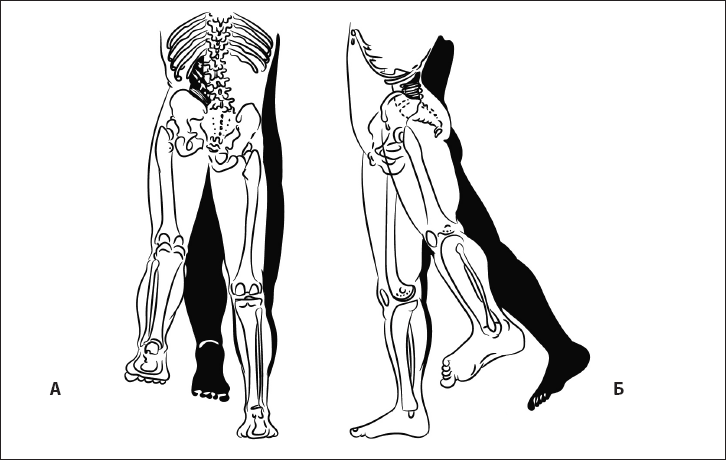

Когда ребенок долго лежит на спине, он пытается перевернуться. Его побуждает к этому рефлекс переворачивания (рис. 17).

Он состоит из координации нескольких движений: разворот ног, поворот туловища, разворот плечевого пояса и поворот головы. В дальнейшем эта последовательность движений реализуется при формировании спиралевидной МФЦ. Она начинается от боковых мышц стопы и заканчивается на руке и шее.

Патобиомеханика. Если по какой-либо причине выключаются мышцы, составляющие одну из цепей, возникает деформация статики в виде бокового смещения таза, мышечно-тонического сколиоза, наклона головы в сторону. Поэтому, чтобы убрать одну из найденных деформаций, необходимо восстановить полноценность МФЦ.

Рис. 17. Рефлекс переворачивания.

При переворачивании на живот ребенок вытягивает ноги, разгибает туловище и далее разгибает голову (рис. 18).

Рис. 18. Рефлекс разгибания головы.

Это движение обеспечивается активацией длинных разгибателей шеи. Благодаря ему ребенок, который лежит на животе, не задыхается.

У взрослого человека он постепенно переходит в рефлекс поддержания головы в вертикальном положении, а мышцы-разгибатели формируют заднюю МФЦ (рис. 19).

Рис. 25. Шаговый рефлекс, или автоматическая походка. А – норма, Б – отсутствие рефлекса.

Рис. 26. При правильном формировании паттерна шага туловище разворачивается навстречу ноге, согнутой в тазобедренном суставе (работа косых мышц живота). А – вид сбоку, Б – вид сзади.